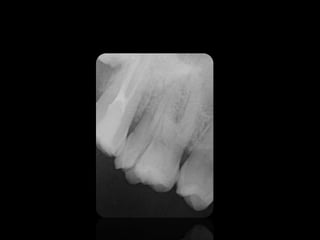

Interpretacion radiográfica

Clase de Interpretación Radiografica presentada por la Dra. Joyce Roca

3.

• Las imagenes

son llamadas radio opacas. • Las imagenes son llamadas radio lúcidas.

REABSORCIONES ÓSEAS

REABSORCIÓN DENTAL EXTERNA